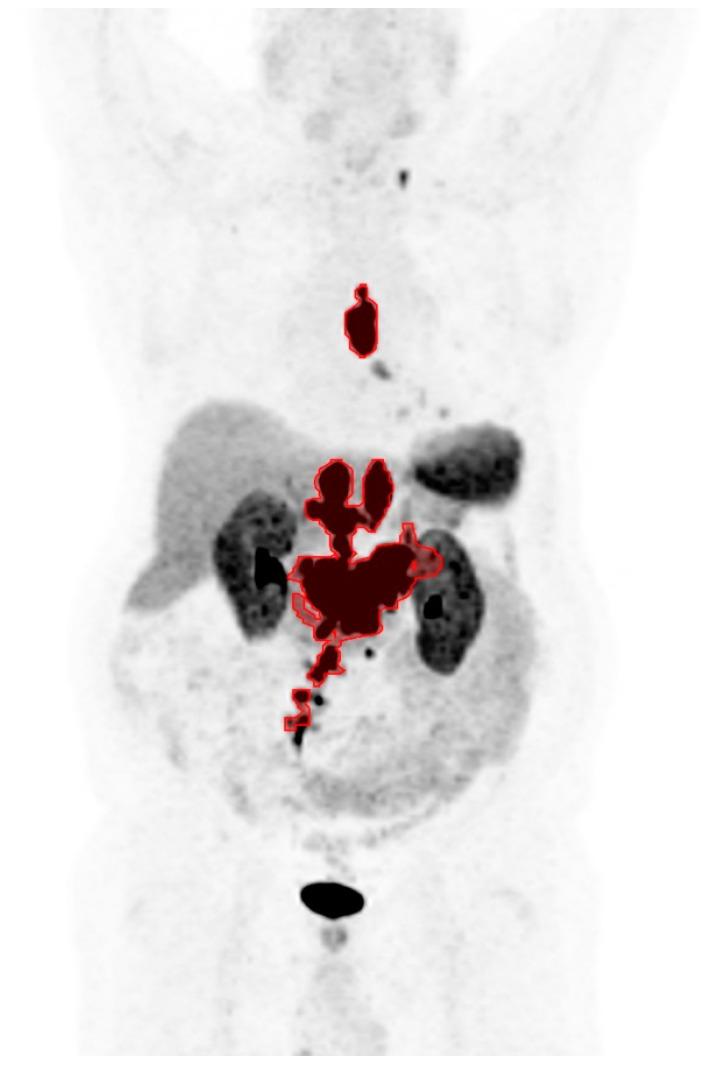

Prediction of Lu-DOTATATE Therapy Outcomes in Neuroendocrine Tumor Patients Using Semi-Automatic Tumor Delineation on Ga-DOTATATE PET/CT.

The medical records of 94 NET patients who received at least one cycle of PRRT at a single institution were retrospectively reviewed. On each pre-treatment Ga-DOTATATE PET/CT, the total tumor volume (TTV), maximum tumor standardized uptake value for the patient (SUVmax), and average uptake in the lesion with the lowest radiotracer uptake (SUVmin) were determined with a semi-automatic tumor delineation method. Progression-free survival (PFS) and overall survival (OS) among the patients were compared based on optimal cutoff values for the imaging parameters.

On Kaplan-Meier analysis and univariate Cox regression, significantly shorter PFS was observed in patients with lower SUVmax, lower SUVmin, and higher TTV. On multivariate Cox regression, lower SUVmin and higher TTV remained predictive of shorter PFS. Only higher TTV was found to be predictive of shorter OS on Kaplan-Meier and Cox regression analyses. In a post hoc Kaplan-Meier analysis, patients with at least one high-risk feature (low SUVmin or high TTV) showed shorter PFS and OS, which may be the most convenient parameter to measure in clinical practice.

The tumor volume and lowest lesion uptake on Ga-DOTATATE PET/CT can predict disease progression following PRRT in NET patients, with the former also predictive of overall survival. NET patients at risk for poor outcomes following PRRT can be identified with semi-automated quantitative analysis of Ga-DOTATATE PET/CT.